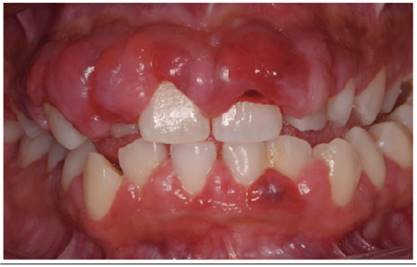

Clinical examination presents a lobulated aspect of the gingiva with severe gingival enlargement with clinical crowns covered to a large extent, showing a bucco-lingual dimension greater than 3 mm and a depth of probing greater than 6 mm (Figure 1). On palpation the gingiva was firm and resilient in consistency. Clinically, the patient still had a visible plaque and visible areas of gingival bleeding (Figure 2a). In the radiographic examination there were no horizontal bone resorptions, either localized or generalized (Figure 2b).